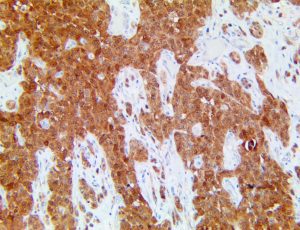

It is the ICU physician who is most likely to witness one of the deadliest manifestations of the abnormal immunological response, the cytokine storm syndrome (CSS). This response is also referred to by some as the cytokine release syndrome (CRS). CSS is characterized by continuous activation and expansion of macrophage and lymphocyte populations, which secrete large amounts of cytokines, causing the cytokine storm. This massive cytokine release is akin to hemophagocytic lymphohistiocytosis (HLH) disease, a syndrome characterized by initial unchecked and persistent activation of cytotoxic T lymphocytes and NK cells.